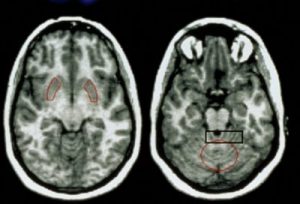

شرب الخمر يقلص حجم الدماغ

كشفت دراسة أميركية حديثة نشرت نتائجها في دورية أرشيف الجهاز العصبي أن شرب الإنسان الخمور بكميات كبيرة من شأنه أن يؤدي إلى تقلص حجم المخ لديه.

بينت نتائج الدراسة التي قام بها باحثون في جامعة ويلزلي بولاية مساتشوستس الأميركية على بيانات 1839 أميركيا بالغا تتراوح أعمارهم بين 33 و 88 عاما أبلغوا عن طبيعة استهلاكهم للكحوليات وأجريت لهم مسوح تصويرية بالرنين المغناطيسي لاظهار حجم المخ أن الأشخاص الذين يمتنعون عن شرب الكحوليات طوال حياتهم يعانون في الواقع أقل خسارة في حجم المخ بينما يعاني المقلعون عن الشرب والمستمرون في الشرب باعتدال والمعاقرون للخمر بشراهة مزيدا من التقلص في حجم المخ.

وأوضحت الدراسة أن هذه النتائج جاءت أكثر وضوحا لدى النساء من الرجال لسبب قد يرجع إلى حساسية النساء الأكبر لتأثير الكحول وحجمهم الأصغر في المتوسط عن الرجال.

وأشارت الدراسة إلى أنه بالمقارنة مع الممتنعين عن الشرب فان الأكثر شربا للكحوليات والذين تم تعريفهم بأنهم يحتسون أكثر من 14 كأساً في الأسبوع لديهم مخ يقل في المتوسط بنسبة واحد في المئة وأن حجم المخ يتقلص بشكل عام بمعدل يقدر بحوالي اثنين في المئة كل عقد.